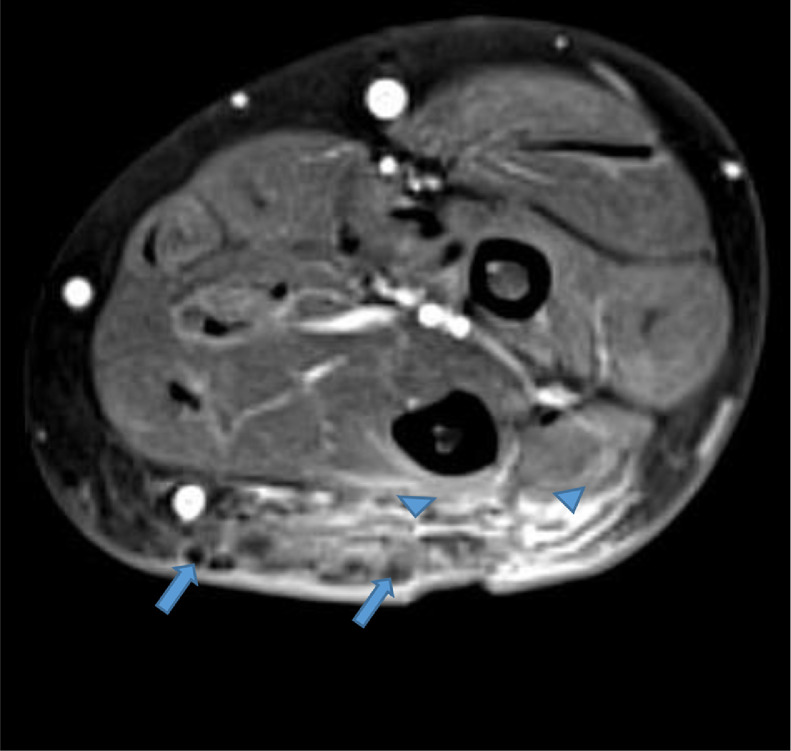

Fig. 7.

Axial T1 fat saturation image with IV contrast reveals intense enhancement in the subcutaneous fat (arrowheads) surrounding the low signal intensity foci in the affected area (arrows). Note the skin thickening overlying the affected area. IV, intravenous